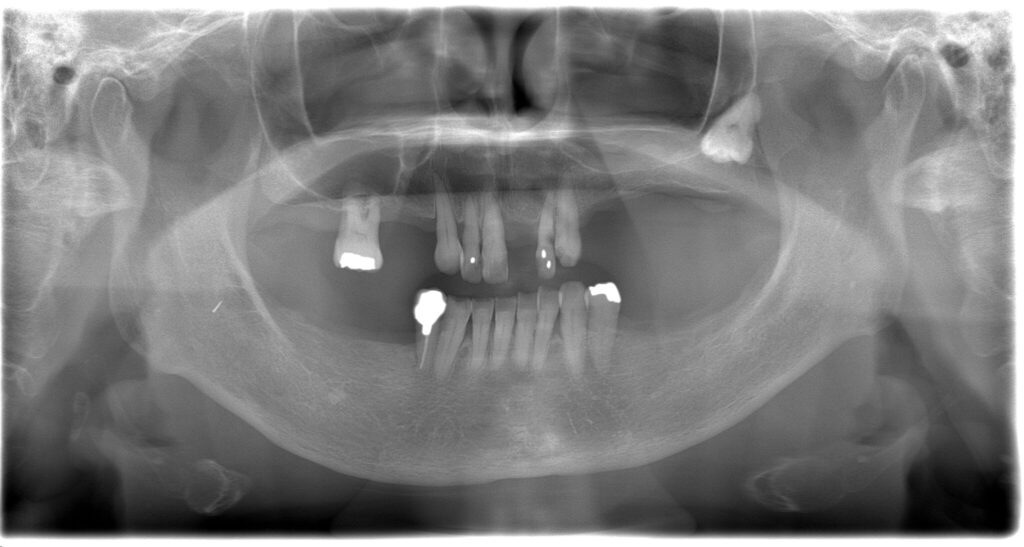

全顎治療症例

| 主訴 | 全体的に見た目を綺麗にしたい。奥歯でしっかり噛みたい。 |

| 診断名・ 主な症状 |

臼歯部欠損 |

| 治療内容 | インプラント埋入(左下5・6,右下5・6,左上4・6) サイナスリフト(左上4・6) ジルコニアBr(右上6−左上3) E –MAX CAD(右下4) セラミックインレー(左下4) |